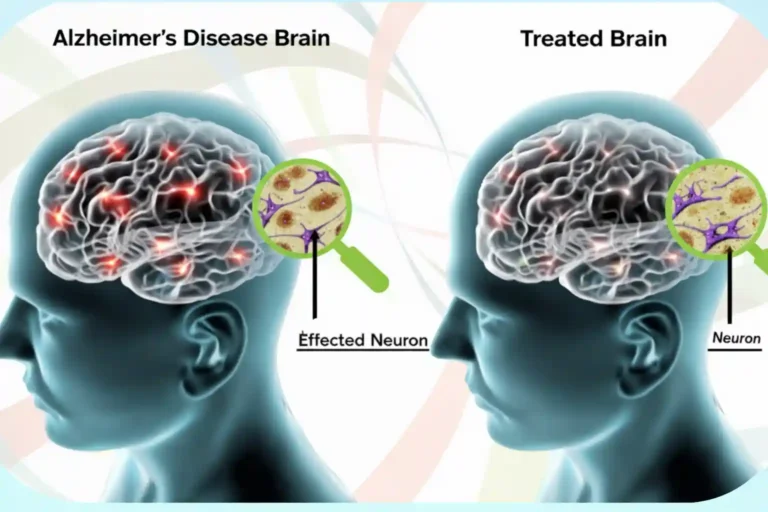

ALZHEIMER’S DISEASE

Definition

Alzheimer’s disease is a progressive condition that affects memory, thinking, and behaviour. It occurs due to gradual degeneration of brain cells.

Common Symptoms

- Memory loss

- Difficulty recognizing people

- Confusion

- Mood changes

- Difficulty performing daily tasks

How Stem Cell Therapy May Help

Stem cell therapy may help support brain cell protection and reduce inflammation. It may enhance neural connectivity and improve cognitive function and quality of life.

Diagnostic Tests

- Cognitive assessment tests

- MRI brain

- Neurological evaluation

- Blood screening

- Memory function scoring

Procedure

- Cognitive and neurological assessment

- Brain imaging review

- Medical clearance

- Targeted stem cell administration

- Cognitive therapy support

- Regular monitoring and reassessment